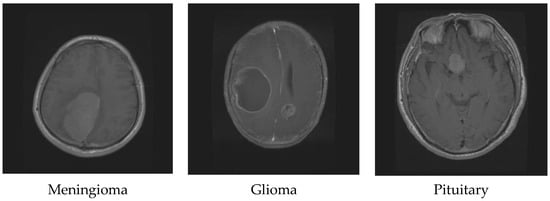

| Tumor Type | Coronal | Axial | Sagittal | Total |

|---|---|---|---|---|

| Meningioma | 268 | 209 | 231 | 708 |

| Glioma | 437 | 494 | 495 | 1426 |

| Pituitary | 319 | 291 | 320 | 930 |

| Total | 3064 |